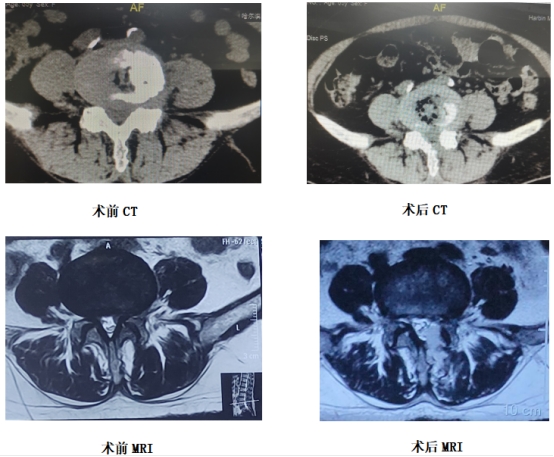

住院后,王岩松教授带领其脊柱微创团队经过进一步详细查体与检查,最终确定王阿姨的诊断为"腰椎管狭窄症,腰椎间盘突出伴神经根病"。考虑到患者年龄大、一般状态较差,基础疾病较多,开放手术与全身麻醉风险极高,加之患者本人强烈排斥开放手术,经过多学科会诊及科室内讨论后,最终决定为患者行微创椎间孔镜手术。术中利用O-arm精准定位,手术切口仅7mm,共耗时50分钟,出血量仅有几毫升,术中及术后无并发症发生。患者术后腰背痛及下肢疼痛麻木症状明显缓解,如今已重新回到家里,恢复了正常的生活。